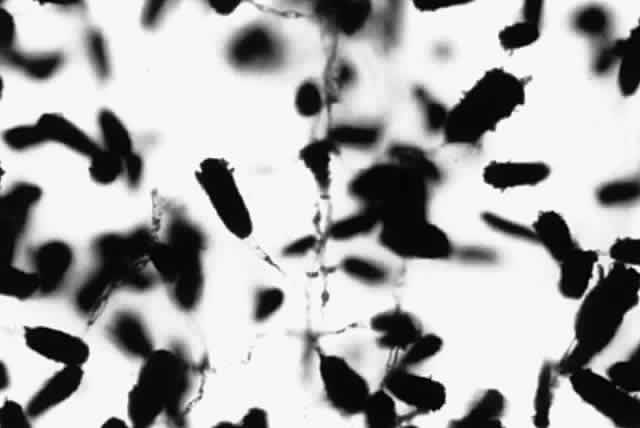

Growth occurs on Sabourauddextrose agar without antibiotics, Lowenstein-Jensen medium, and Middlebrook 7H11 agar and matures within 7 to 9 days. Colonies on Sabouraud dextrose agar are white to orange, raised, irregular or smooth (Fig. 9). Microscopically on tap water agar are seen thin, delicate, branching, beaded filaments that fragment into bacillary or coccoid forms (Fig. 10). They are gram positive and may be partially acid fast. There are three major pathogens to humans: N. asteroides, N. brasiliensis, and N. otitidiscaviarum.

Fig. 10. Growth of Nocardia asteroides on tap water agar showing branching aerial mycelia (X 40).